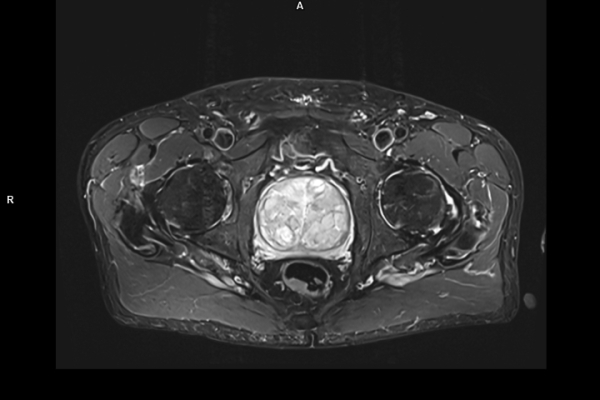

CT Untersuchung Bild

Detailbild MRT